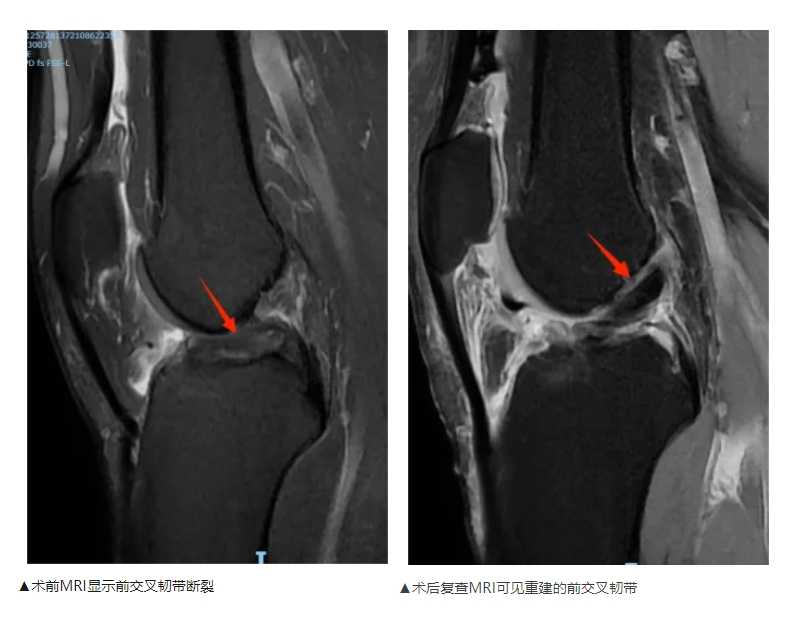

前交叉韧带断裂全内技术重建